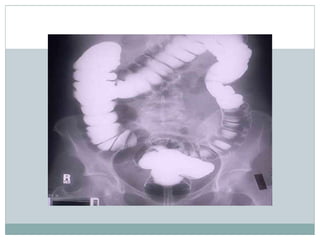

15 min

post

contrast

film